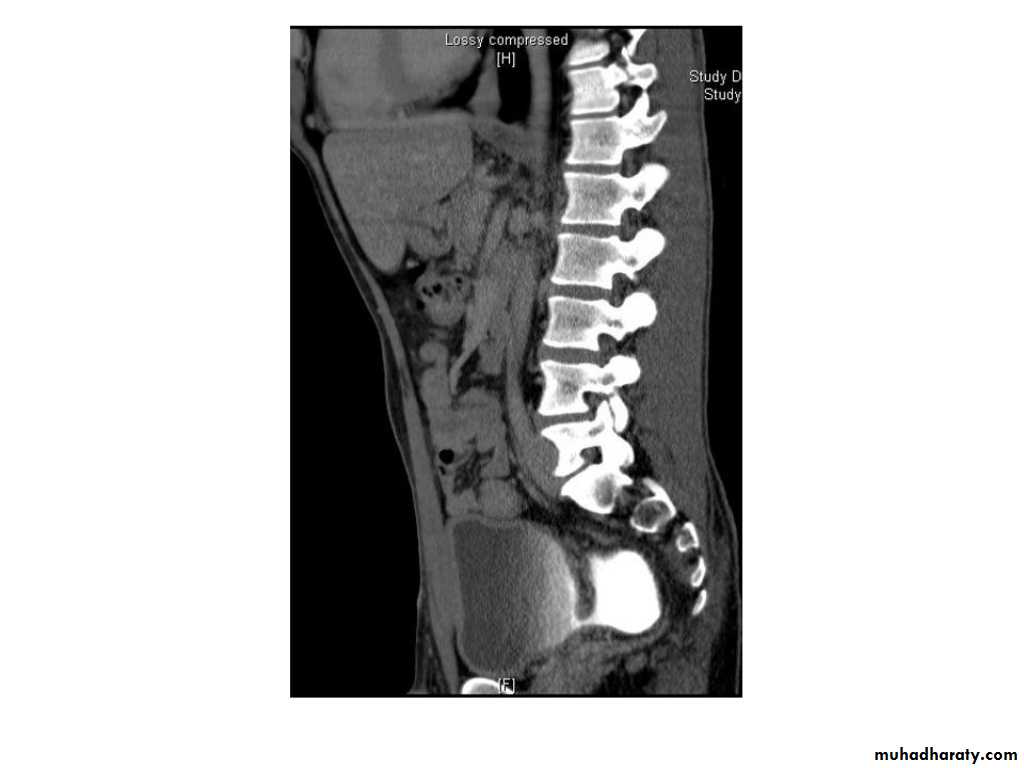

IVU shows

1. The kidneys at low position .2.Close to the spine with long axis parallel to the spine

3. Malrotation manifested by medially directed calyces.

4- The renal pelvis and ureters are anterior and lateral in position.

5- Hydronephrosis and calculi highly associated.